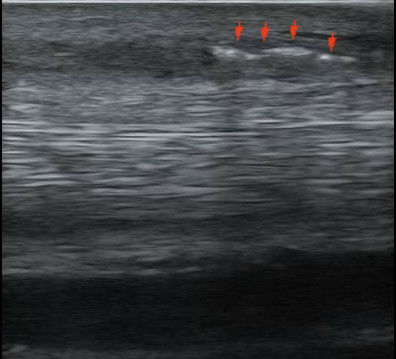

Az ultrahang vezérelt őssejt-oldat befecskendezés ellenőrzése. A piros nyilak a beinjekciózás során bekerülő levegőbuborékokat jelzik.